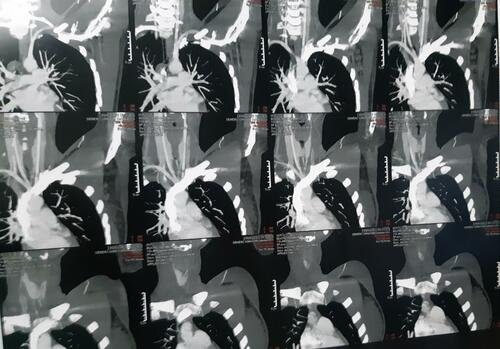

Ao se passarem 3 meses, retornei ao médico com novos exames, já curada da trombose de membro superior, recebi a notícia de uma compressão arterial, mais especificamente Síndrome do Desfiladeiro Torácico. Em exames mais específicos, descobriu-se também uma Costela Cervical, que ajudou para com a compressão da artéria.